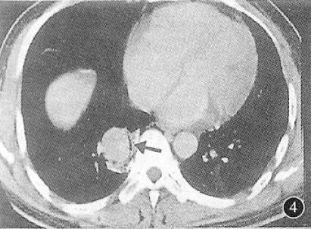

例2:患者肺结核,咯血

图4 胸部CT

图4 胸部CT诊断:肺结核合并曲霉球。

肺结核空洞,长曲霉球,不少见。肺结核空洞内的球会随着体位变动。患者出现反复大咯血,需要手术切除。